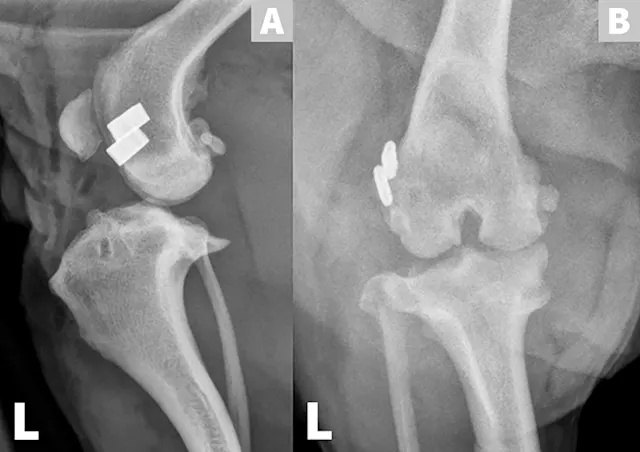

This image gallery reviews some surgical options for cranial cruciate ligament (CrCL) injuries in dogs, including the lateral fabellotibial suture (LS), tibial plateau-leveling osteotomy (TPLO), cranial tibial closing wedge ostectomy (CCWO), and tibial tuberosity advancement (TTA).